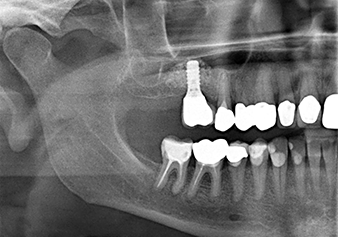

Following an intermediate check (Fig. 4) a further preparation step was performed (Fig. 5). Afterwards, the hydraulic Z35P instrument was used to lift the membrane to the desired position (Fig. 6 and 7). This was followed by further piezosurgical preparation of the implant bed, concluded with a rotary bur and shoulder milling cutter up to the implant diameter of 4.8 mm. Before the implant was inserted, the augmentation material (particle size approx. 0.8-1.6 mm) was introduced underneath the Schneiderian membrane (Fig. 8).